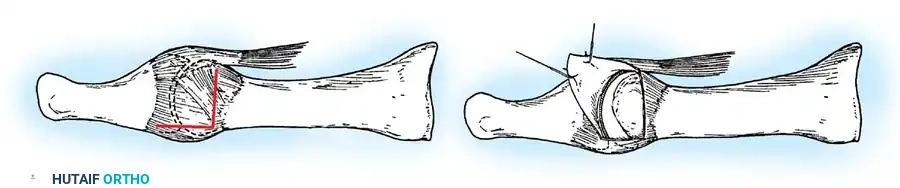

• Close the capsule with interrupted 2-0 or 3-0 absorbable sutures. A fi rm, complete capsular closure is imperative. A box stitch is recommended. Increasing the curve of the needle manually is helpful.

• Starting proximal and plantarward, pass the suture through the capsule from the outside in.

• The second pass of the suture is from the inside out through substantial soft tissue on the plantar medial aspect of the phalangeal base.

• Reenter the soft tissue at the base of the proximal phalangeal remnant dorsomedially for the third pass. Move the suture back and forth to ensure uninhibited excursion.

• Make the fourth pass from inside out through the dorsal capsule in line with the initial plantar capsular suture. Have an assistant grasp the ends of the capsule, pulling them together, while the tie is completed. This is basically a four-corner box stitch, which may leave a small area of capsule in the middle that cannot be approximated, but this is of no consequence.

• Intersperse interrupted sutures as needed to complete a fi rm closure.

• Close the capsule with a purse-string suture as previously described in the original technique (Fig. 78-31H to J).